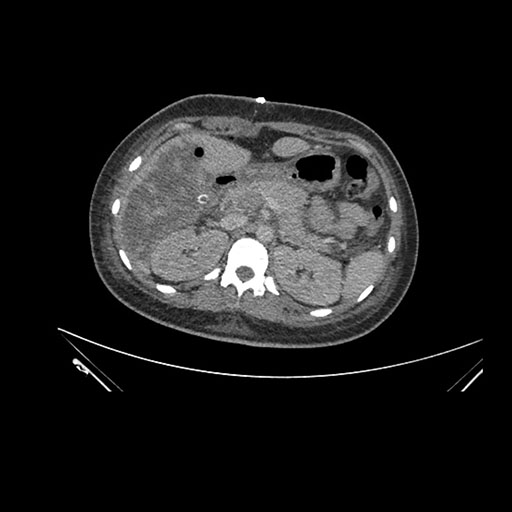

Imaging Analysis

Look through the patient's CT scan to identify any areas of concern for the necessary procedure.

Axial Venous

Based on initial findings, which issue(s) would you be most concerned about?